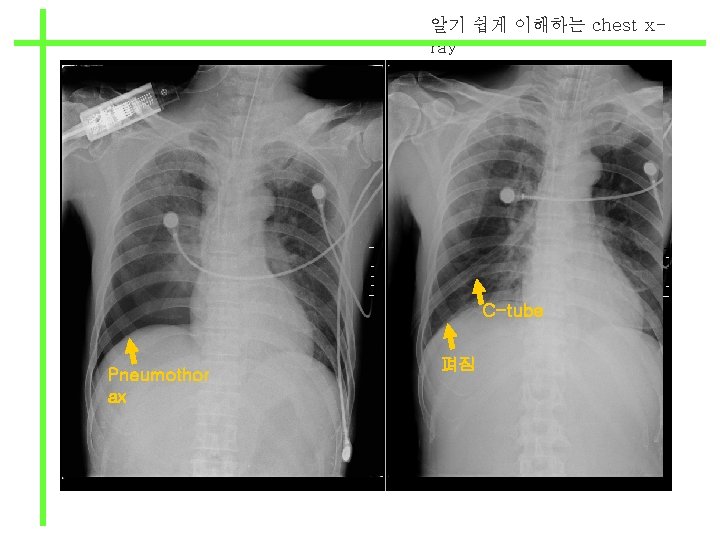

알기 쉽게 이해하는 chest xray C-tube Pneumothorax 펴짐

알기 쉽게 이해하는 chest xray C-tube Pneumothor ax 펴짐